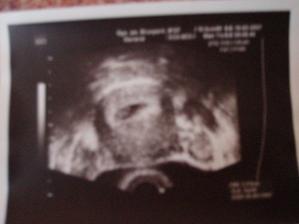

Tak i konečně já přidávám pár svých fotek a postupně budu přidávat další🙂)na prvním utz (fotce) ještě není moc vidět, ale máme srdíčko, jupíííí, zato na druhé už se nám budulínek pořádně ukázal, hip hip hurá🙂))